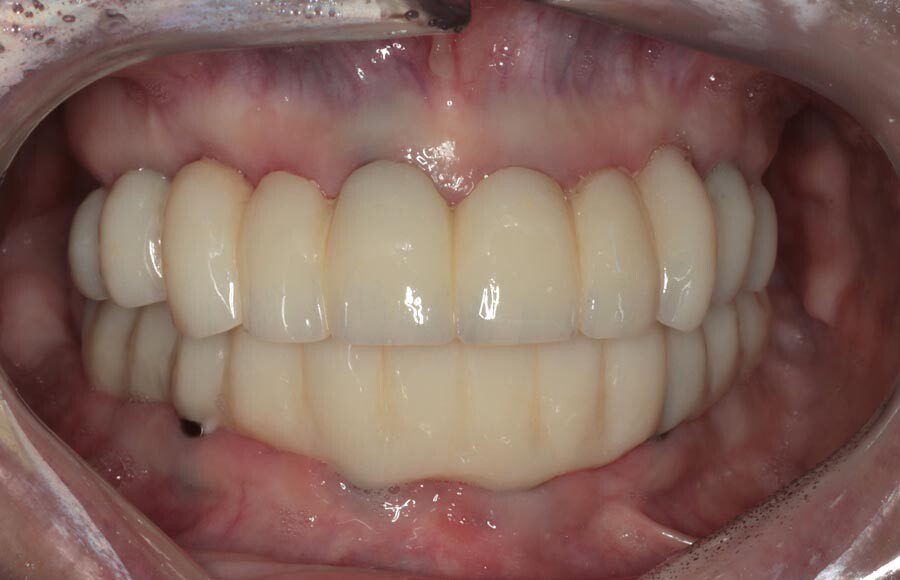

The definitive bridges are delivered, the bite is verified, and the screws are torqued down firmly. The final result is strong, functional, and esthetic restorations that will serve the patient well for years to come.

The patient couldn’t be happier with her new smile. We have improved not only her esthetics but her oral health as well. She now has beautiful restorations she can keep for years to come. Contact us if you would like to have a consultation and see if this is the right treatment for you!